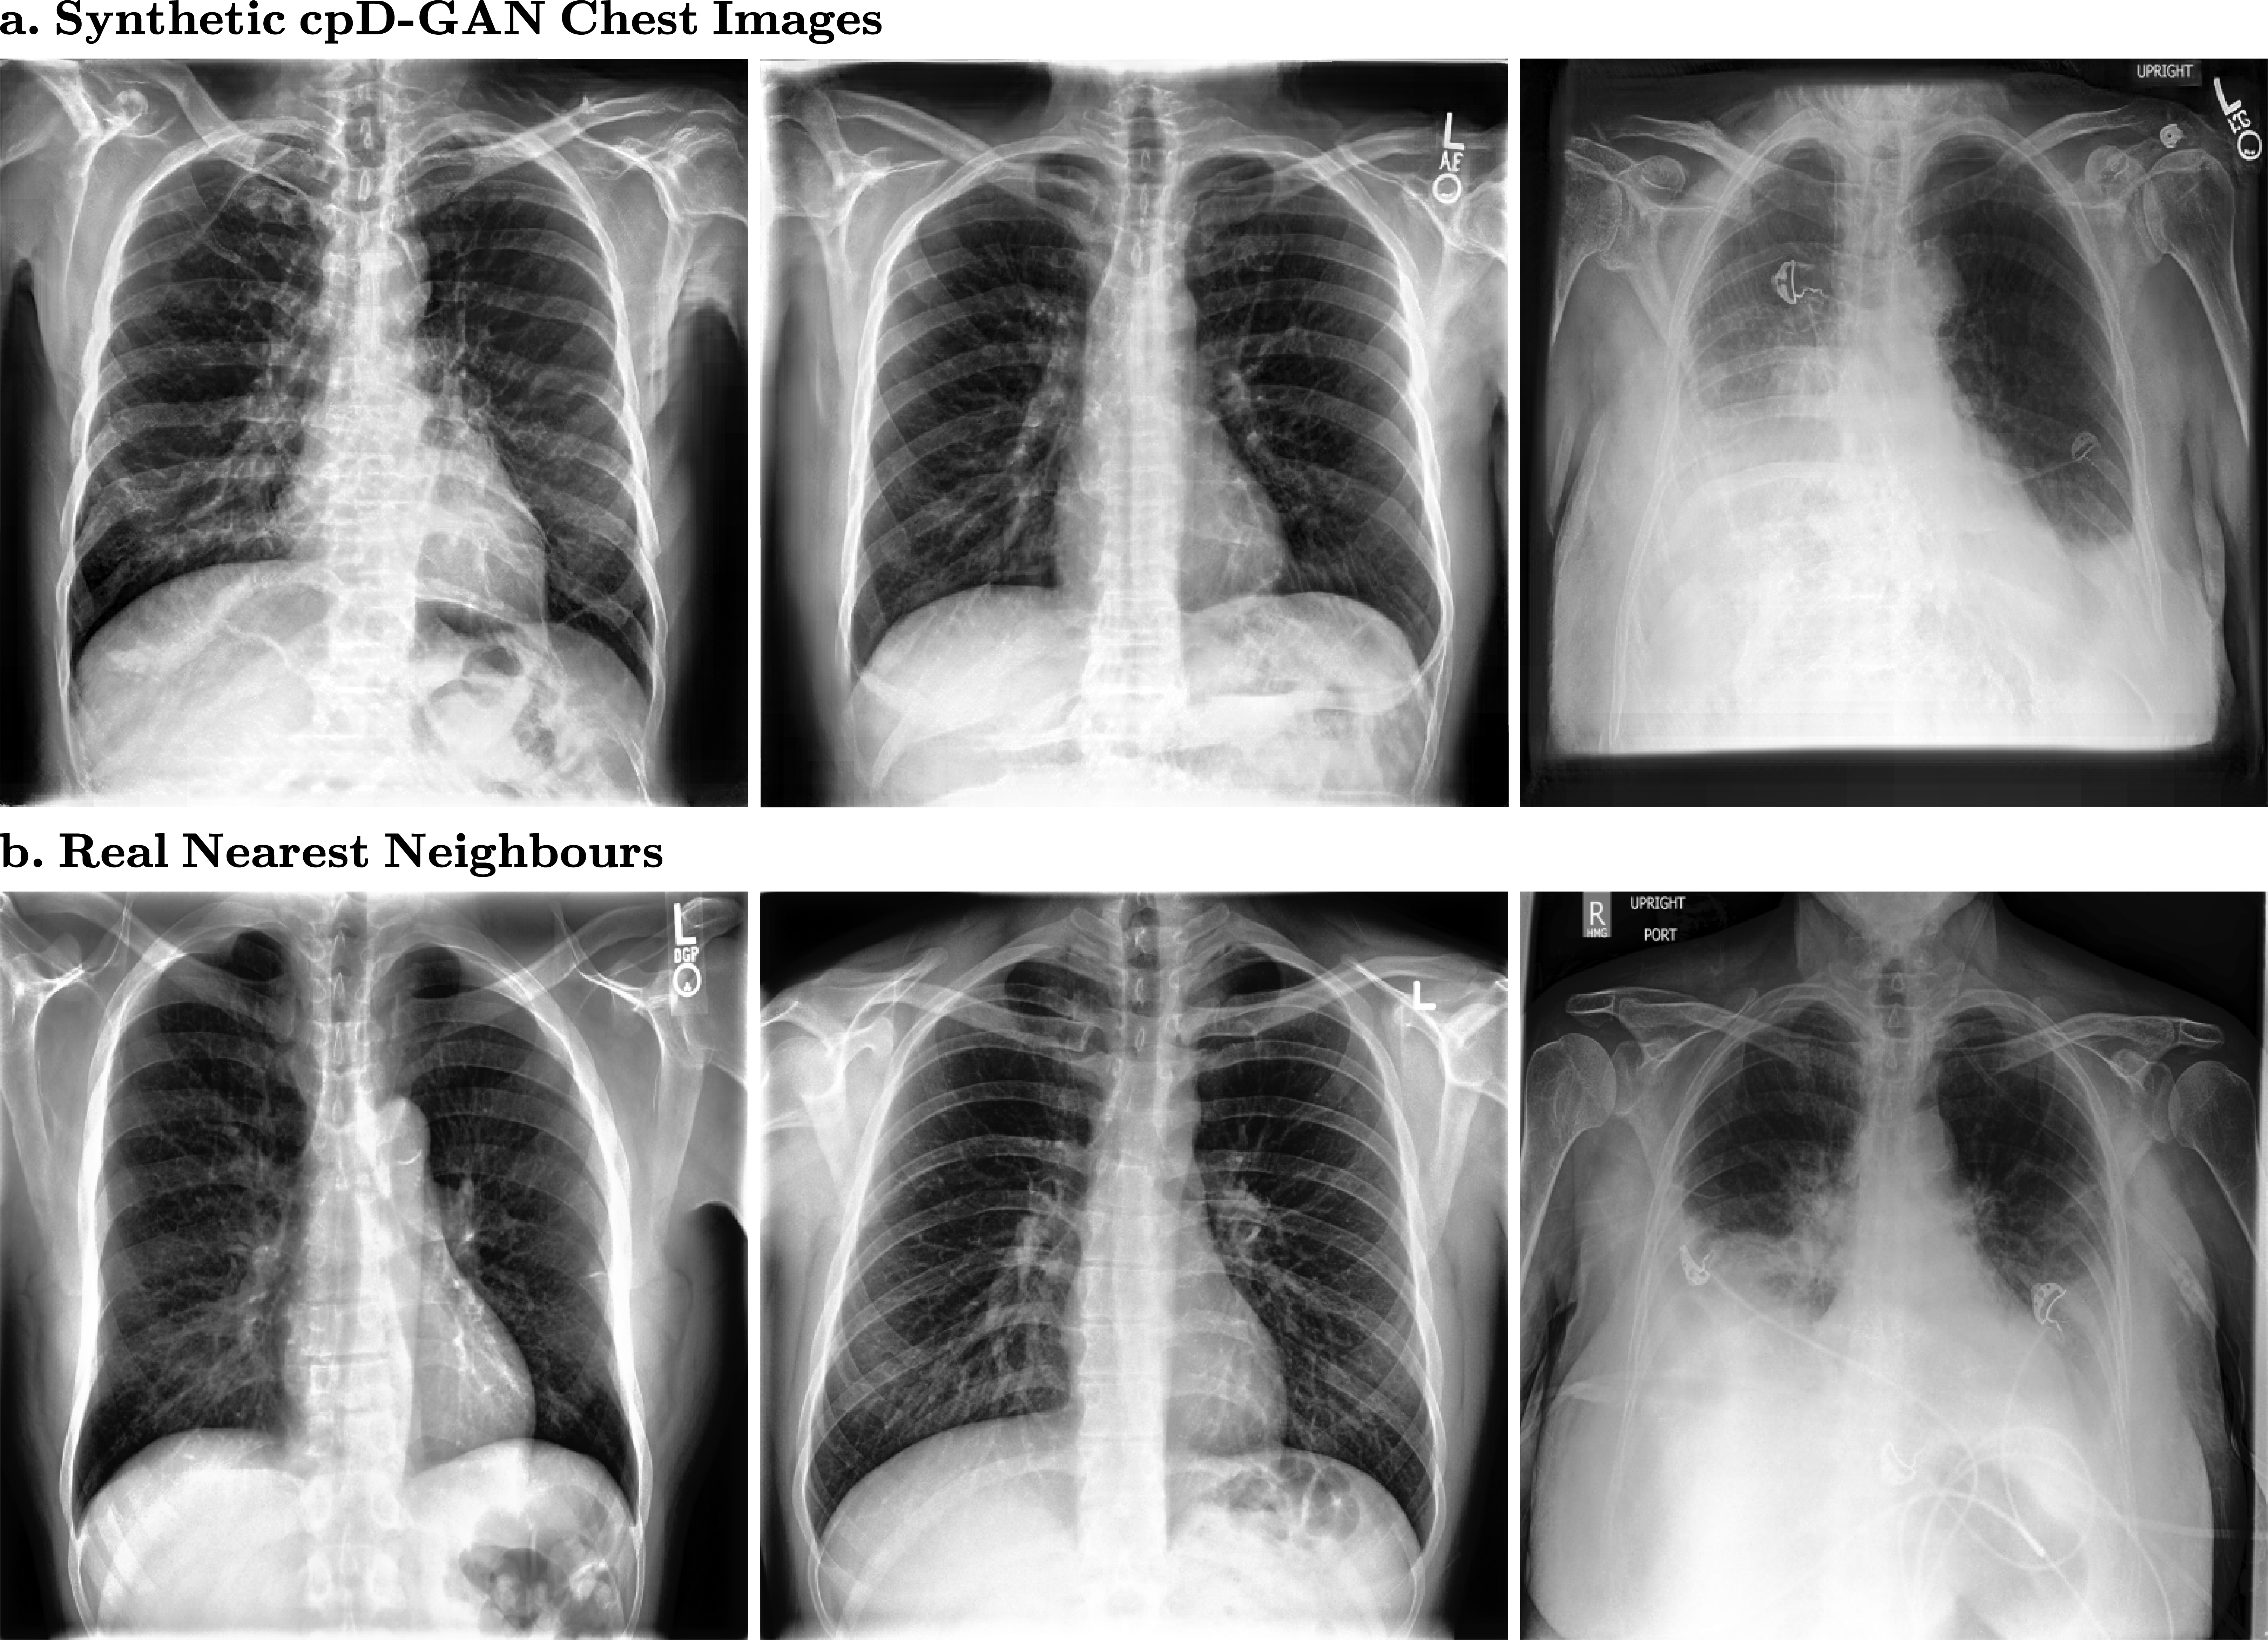

Figure 3:

(a.) Synthetic chest x-rays and (b.) closest matching real nearest neighbours at a resolution of 512 x 512 pixels

The quality of the chest x-rays in Fig. 3 also appears to be close to the quality of real data, without simply copying training images. However, for the support devices class, we observe visual artefacts in the synthetic x-rays. The GAN model fails to realistically generate tubes and other support devices, such as pacemakers or defibrillators, as shown in Fig. 4. These devices deviate strongly in their visual appearance when compared to the physiological chest outlining and were not accurately learned by the generative model. Crucially, our benchmark successfully captured the drops in visual quality due to the support devices class at higher resolutions.